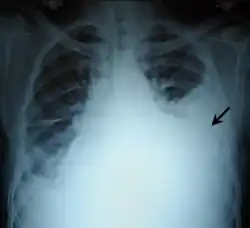

| Left tension pneumothorax with a large, well-demarcated area devoid of lung markings with tracheal deviation and movement of the heart away from the affected side. |

Tension pneumothorax

Tension pneumothorax is an emergent condition in which air gets trapped in the space between the chest wall and the lung. This space is referred to as the pleural space. Because air can't escape from this space, the air pocket grows larger and larger, resulting in the lung collapse closest to the pneumothorax. Forces are transmitted to the mediastinum and effectively "push" the mediastinal structures to the opposite side of the chest.[5]